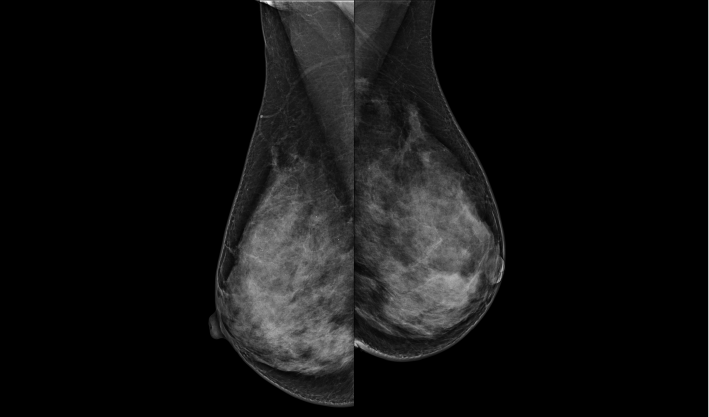

致力于致密乳腺的早期癌變篩查和微鈣化簇精準定性。